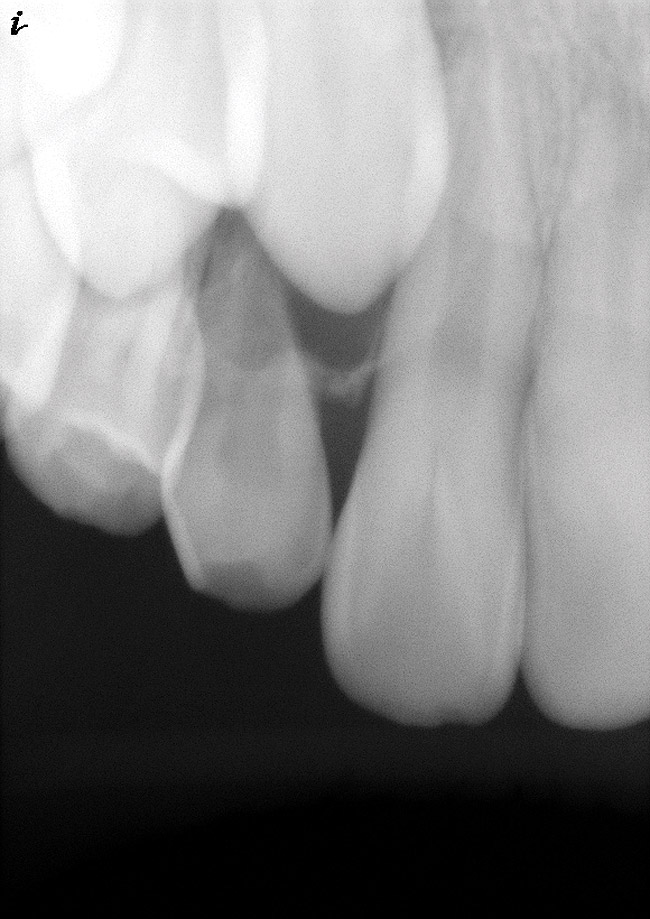

Figure 6  Root resorption secondary to orthodontic tooth movement.

Figure 6